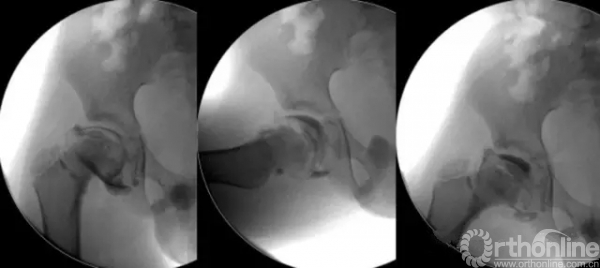

答:1)髋脱位闭合复位造影时,维持髋关节于脱位状态(髋关节屈曲外展但股骨头不要复入臼内);2)经髋关节前侧穿刺时针尖应位于大小转子上缘连线以近(关节囊下缘水平);3)不管那种方法,在针头突破关节囊时经常会有“落空感”,可以回抽一下看是否有丝状关节液,然后试着推入少量造影剂,如果阻力不大、造影剂迅速沿关节囊轮廓扩散开(俗称“冒烟”)而不是呈局部会聚就可以确认在髋关节内;4)维持注射器负压状态拔出针头。也有医生习惯于复位状态穿刺,根据“复位——脱位”时注射器尾端是否有“负压”形成来判断。

答:Good question。和闭合复位类似,对于小年龄髋脱位切开复位后同样可以借助关节造影判断复位质量。常规方法很容易发生造影剂外溢,可以通过“涂抹造影剂”的方法显示股骨头软骨轮廓,也可以在关节囊重建前预留细软管,关节囊缝合后再打入造影剂。